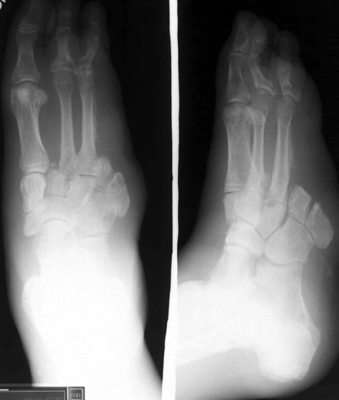

Boarder ray amputations do not significantly interfere with

ambulation. In fact, amputation of the lateral two or even three rays often provides

a functional weight-bearing foot. Amputation of the medial two and even three rays

in special circumstances may provide a weight-bearing, sensitive, reasonably functional

foot (See below).